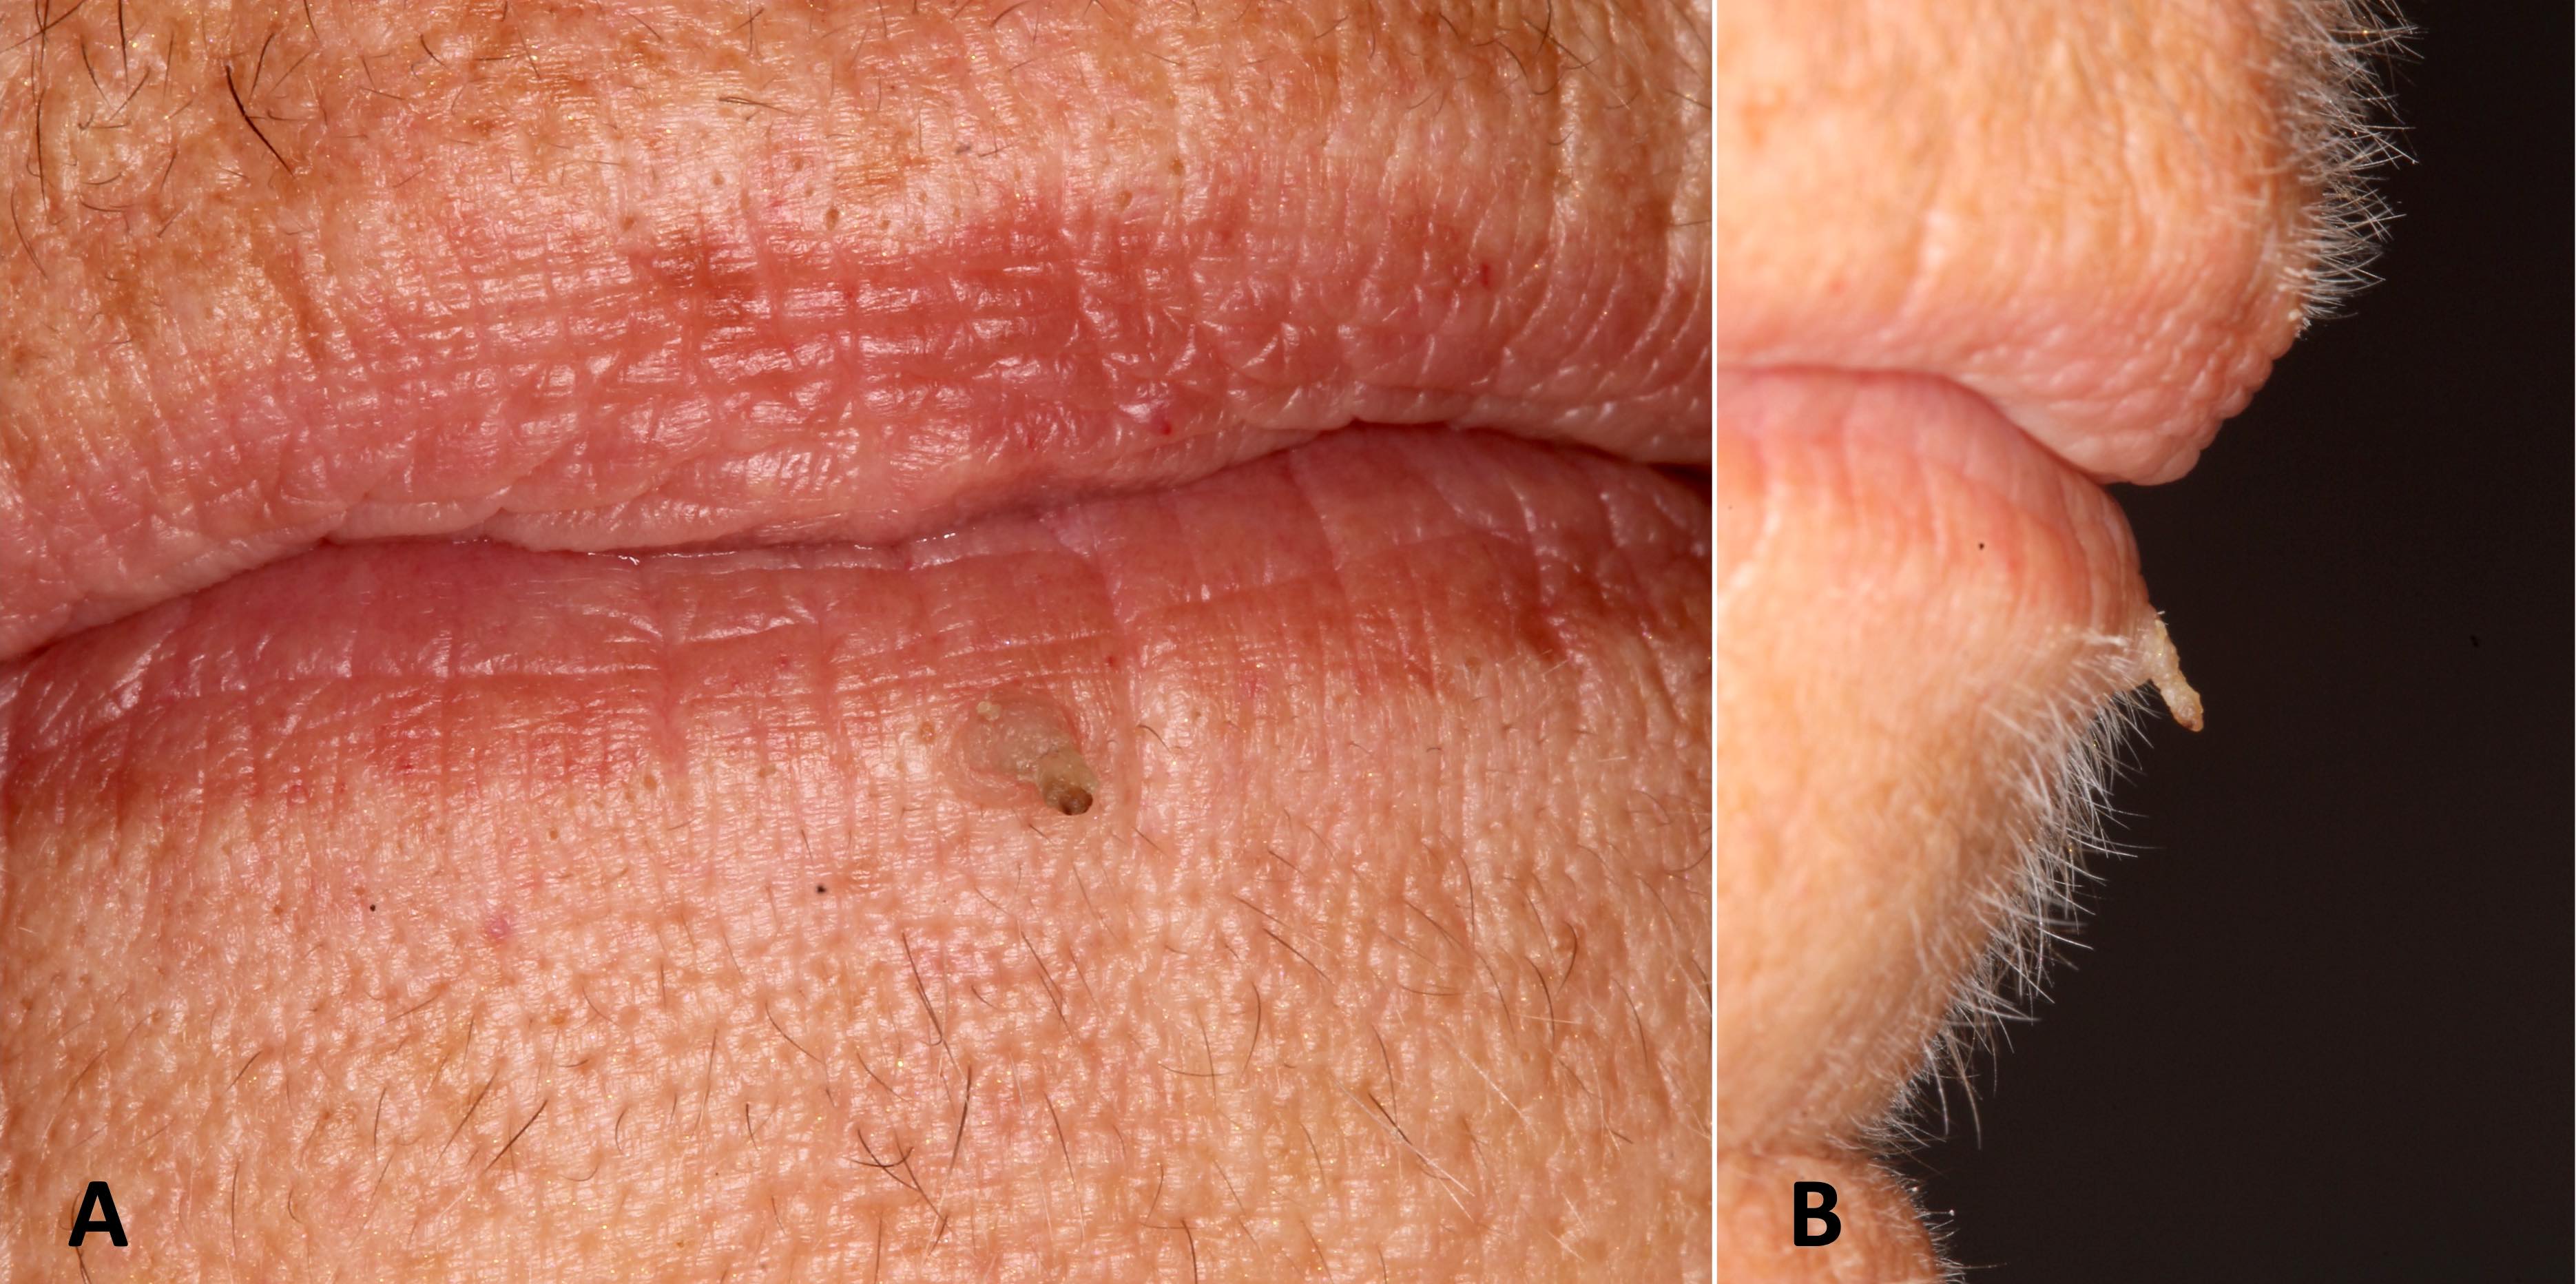

- Similar to cutaneous counterpart (Head Neck Pathol 2019;13:80)

- Asymptomatic, well delineated, often white papule or nodule with a papillary or pebbled surface

- Sessile or pedunculated

- May demonstrate a keratin horn

- Most are single lesions but multiple may occur (Atlas Oral Maxillofac Surg Clin North Am 2017;25:163)

- < 1 cm in diameter (Head Neck Pathol 2019;13:80)

- 18 year old man presented with verruca vulgaris lesions on the fingers and lips (J Cutan Med Surg 2017;21:251)

Clinical images